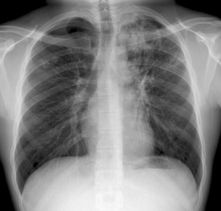

白色瘟疫——结核病

。肺结核病占各种类型结核病的80%以上,且肺结核是结核病传染的主要类型。